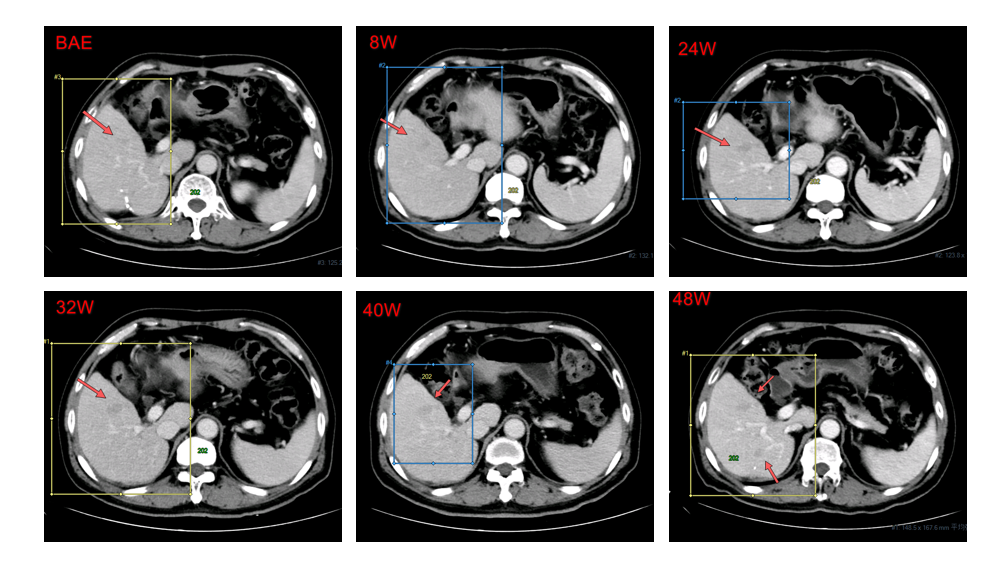

2016年4月13日,接受原发肝癌切除术,术程顺利。术后复查确认复发。2016年12月30日,首次服用多纳非尼(0.2g,每日两次)治疗,8周后经疗效评估为疾病稳定(SD)。随后继续使用,靶病灶持续稳定。经独立评审委员会(IRC)评估的无进展生存期(PFS)为7.5个月,而由研究者评估的PFS为11.2个月。

肝右叶非靶病灶影像学改变:8-48w为SD